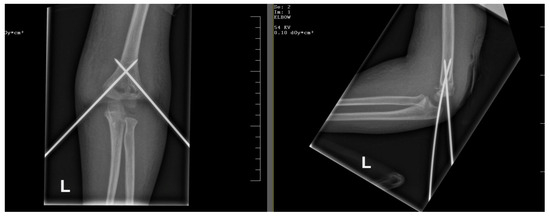

Closed Reduction with Percutaneous Kirschner-Wire Pinning